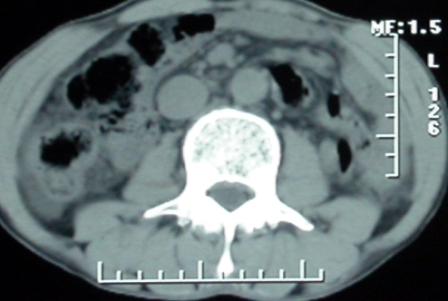

作者: rsyby 时间: 2006-11-28 22:53

标题: 上腹隐痛、饱胀、消瘦2-月。

增强ct所见

门脉主干及肠系膜上静脉近端明显增粗,尤其前者呈等低混杂密度,增强后周围见轻度环形强化。明显占位效应。肝内外胆管见大量气体影。胆囊明显增大。

考虑:1、门脉栓塞; 2、肝内外胆管积气。